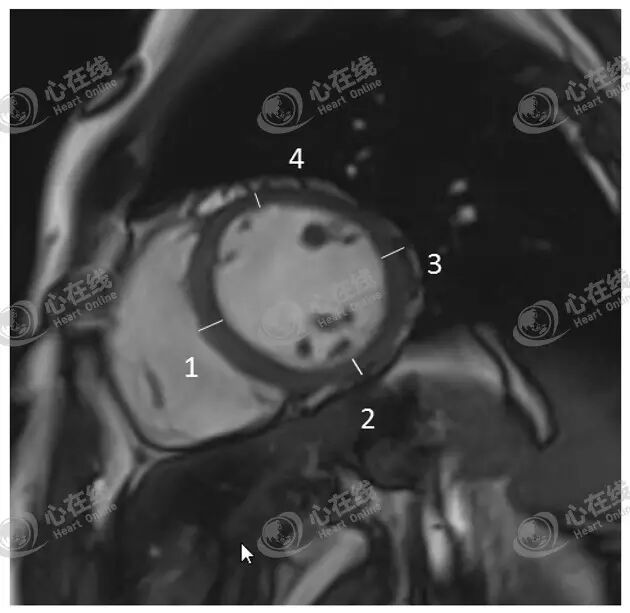

3、左室室壁厚度测量

如图9,一般在TrueFISP左室舒张末短轴图像的肌平面上,选择左室的间隔壁(直线1)、下壁(直线2)、侧壁(直线3)和前壁(直线4)进行测量。更详细的测量可依据美国心脏病协会公布的“17节段分法”(详见:

图9